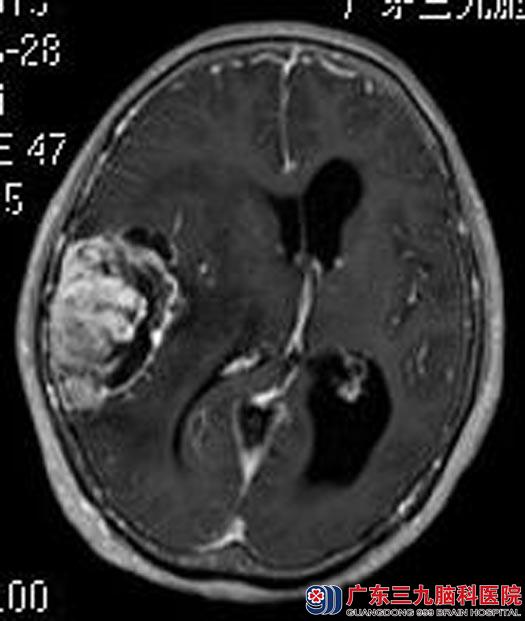

一听到医生说可能是恶性肿瘤,丘女士仿佛瞬间落入万丈深渊,似乎已经看到了生命的尽头。在丈夫的反复劝说下,他们来到了广东三九脑科医院神经综合神经外科。头颅MR进一步检查提示:右侧颞顶部占位性病变,大小约52.3mm×42.2mm×63.9mm,考虑脑膜瘤。在进一步检查考虑良性病变后,丘女士重拾战胜疾病的信心,要求手术治疗。

▲手术前